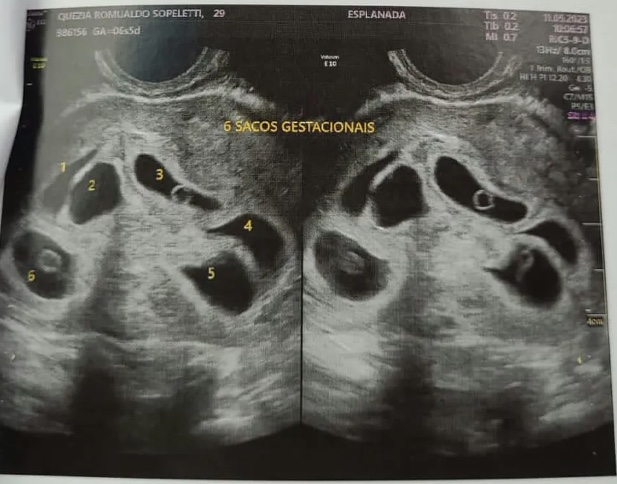

A dona de casa Quezia Romualdo levou um grande susto ao descobrir durante um exame de ultrassonografia que estava gerando não apenas um bebê, mas seis crianças. O caso aconteceu em Colatina, no Noroeste do Espírito Santo.

Na sexta-feira (12), que antecedeu o Dia das Mães, ela foi ao obstetra fazer os primeiros exames da sua segunda gestação, e e até o momento, achando que só havia um bebê em seu ventre.

A mulher, que estava empolgada, foi ficando supresa quando a médica começou a contar os fetos.